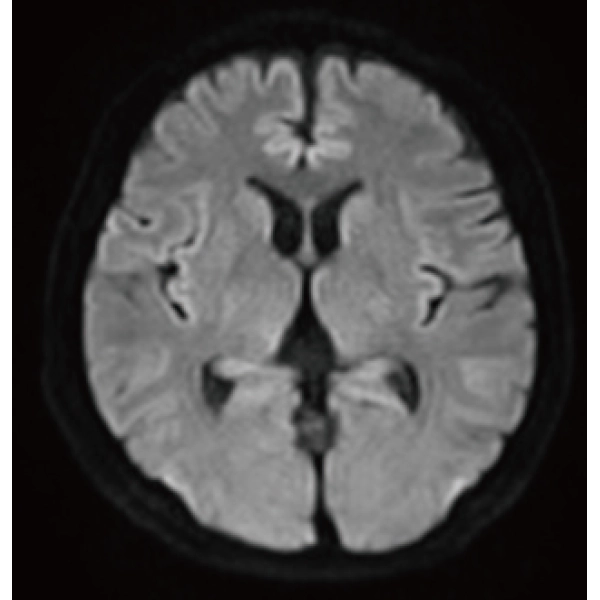

"DLR" is applicable to all body parts and promotes high speed imaging and diagnostic efficiency

IP-RAPID x DLR Plus can also shorten imaging time, allowing more images to be taken in the same examination time.

Additional imaging, such as different image types and cross sections, can be added to the conventional examination to increase the amount of information and make the diagnosis more reliable.